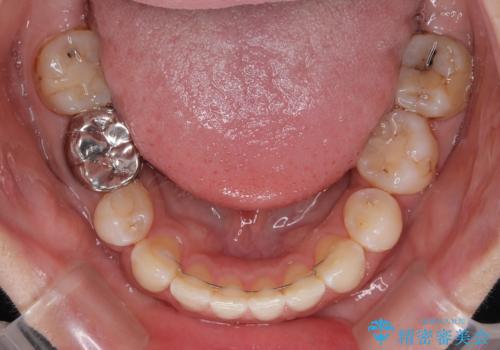

- 口元の突出感と奥歯のむし歯を気にして来院された患者様です。

奥歯の虫歯は事前に矯正治療用の仮歯に置き換えて矯正治療を行い、装置除去後にセラミッククラウンにて補綴治療を行うこととしました。

通常は上下左右の第一小臼歯4本を抜歯することになりますが、左側下顎の第二小臼歯は既に根管治療をされており、予後が良くないとのことでこの歯を抜歯し、ワイヤー装置にて矯正治療を行うこととしました。

第二小臼歯抜歯はイレギュラーな治療手段であり、治療期間が延びる傾向にありますが、予定よりも早い2年間で終えることができました。